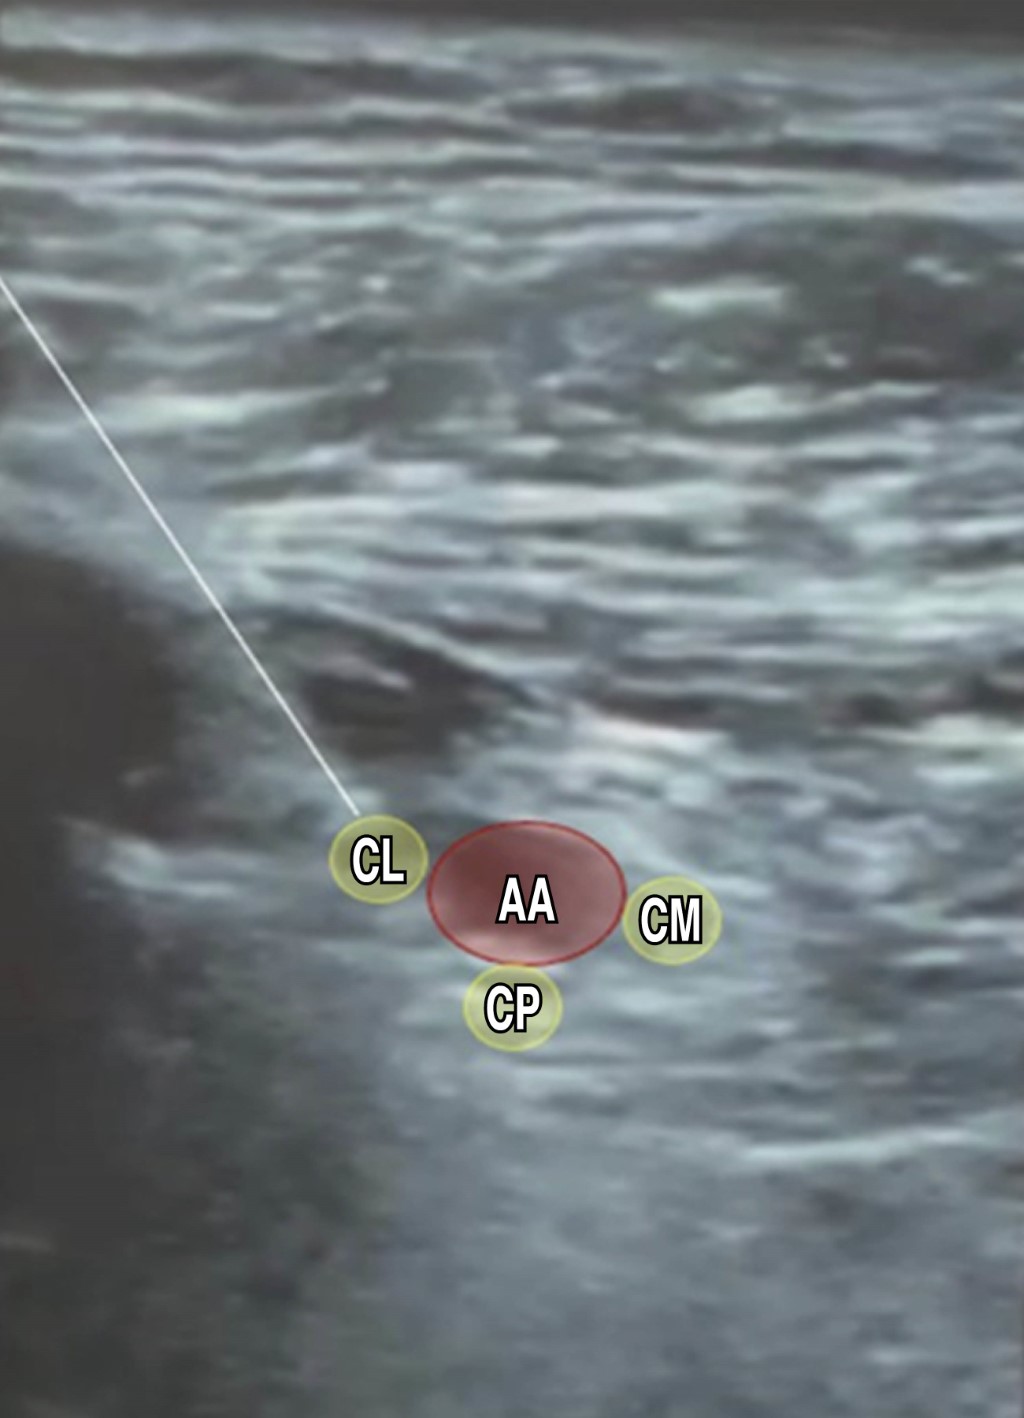

Ultrasound-guided bilateral brachial plexus block, supraclavicular and infraclavicular approach in upper limb surgery plus ultrasound-guided monitoring of diaphragmatic dynamics. A case report

Introduction: in anesthetic practice, bilateral brachial plexus block (BPB) is generally contraindicated due to the risks it entails, systemic toxicity from local anesthetics and bilateral phrenic nerve palsy. Since its indications are scarce, we present the case of a patient who was managed with bilateral regional anesthesia for both upper limbs at the same surgical time. Case presentation: 60-year-old male patient with diagnoses of Frikman III right distal radius fracture and Mayo III left olecranon fracture, scheduled for open reduction and internal fixation (ORIF) of the left olecranon and of the right distal radius, history of type 2 diabetes, systemic arterial hypertension and compensated chronic heart failure. Interventions: left supraclavicular and right infraclavicular BPB were performed as the only anesthetic procedure for bilateral upper limb surgery. Results: bilateral BPB was successful for bilateral upper limb surgery. The surgery was uneventful and without major complications. Conclusions: bilateral brachial plexus block is a safe technique when performed in different approaches, trying to minimize the risk of complications, providing better comfort in the immediate postoperative period of the patient by providing prolonged analgesia.

Figure 2